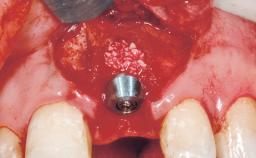

A 30-year-old female patient was referred to the office for the treatment of tooth 11. Her chief concern at the initial visit was to inquire, “Why is my tooth pink?” Upon clinical examination, it was determined that tooth 11 had a previous history of trauma and that the clinical crown had become noticeably pink in color as a result of internal resorption. This diagnosis was confirmed radiographically, indicating a large radiolucency involving the central and distal portions of the clinical crown. It was determined that restoration of this tooth was not possible, and that extraction was indicated. The presence of a mid-line diastema, which the patient wanted to reproduce, directed the treatment plan for tooth replacement utilizing a dental implant.

Type of Implants One-Piece|Reduced-Diameter

Bone Augmentation Horizontal|Simultaneous

Augmentation Materials Autogenous chips|Membrane

Abutment Type Standard

Placement Protocol Immediate implant placement

Socket Integrity Sufficient, with intact bone walls

Bone Volume Sufficient, with intact walls